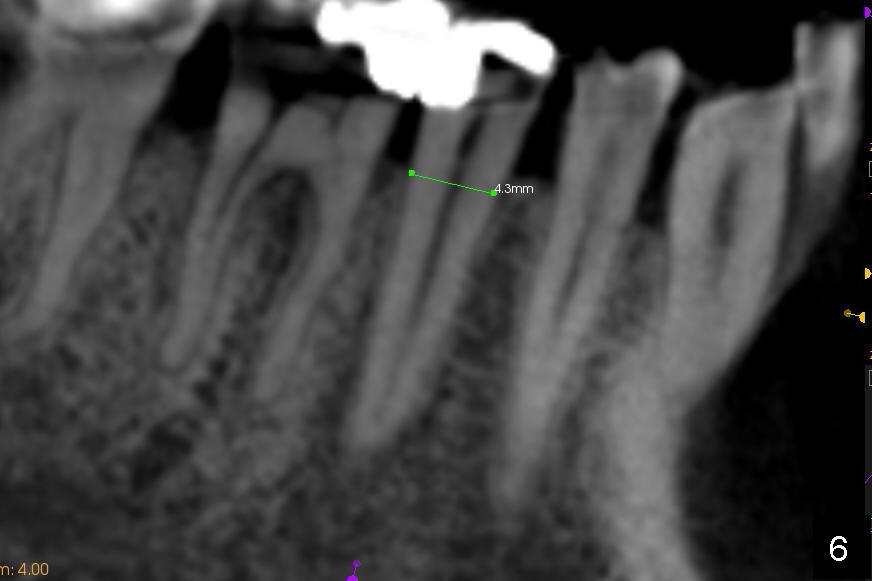

下颌第二前磨牙CT矢状切面显示近远中宽四毫米(图六),冠状切面显示颊(图七B)舌(L)侧宽约六毫米(图八),颏神经襻(*)颊侧比舌侧高,如果即刻植牙偏向舌侧(图九红色),颏神经受损可能性减少。如果即刻植牙局限于拔牙窝(图九虚线),那么更安全(1 2)。